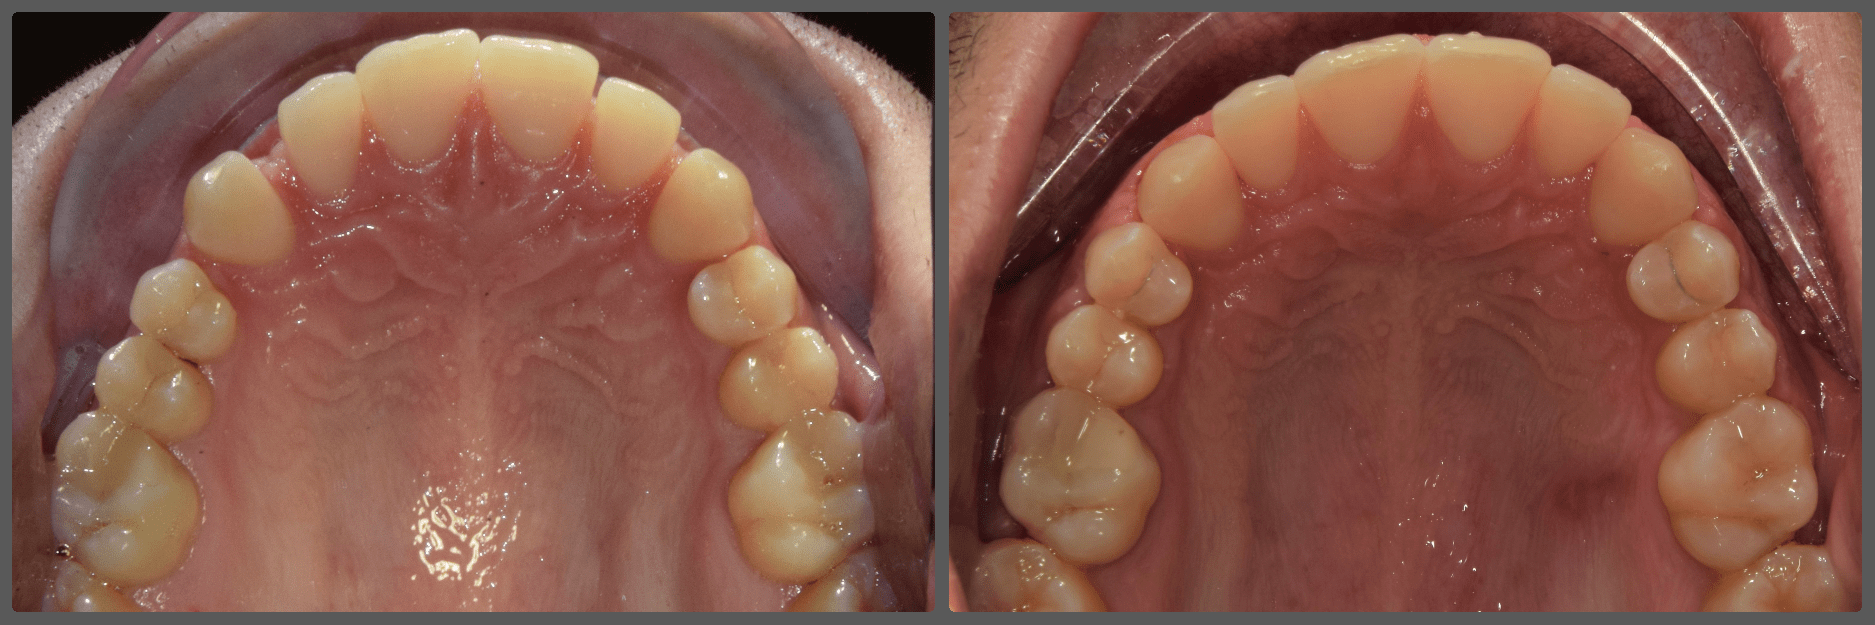

Bálint a 90 fokban elfordult jobb felső kismetszője miatt keresett meg engem. A vizsgálatokat követően kiderült, hogy a probléma ennél jóval komplexebb: súlyos keresztharapást, súlyos mélyharapást és felső rágósík billenést diagnosztizáltam nála. Alsó-felső H4 önligírozó fogszabályozó készülék, intermaxilláris gumihúzás és elülső harapásemelők segítségével korrigáltuk az eltéréseket. A bal oldali rágósík billenést fogszabályzási miniimplantátum alkalmazásával oldottuk meg. A bal felső-elülső fogakat felfelé mozgattuk, a miniimplantátumhoz húzva. Bálint esete igen komplex volt, ám kiváló együttműködésének köszönhetően 26 hónap alatt végeztünk a kezelésével (beleértve a 2-3 hónapos COVID-19 miatti leállást is). Az eredmény úgy gondolom magáért beszél!